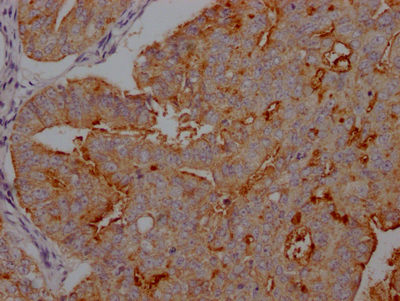

IHC image of CSB-RA941216A0HU diluted at 1:100 and staining in paraffin-embedded human endometrial cancer performed on a Leica BondTM system. After dewaxing and hydration, antigen retrieval was mediated by high pressure in a citrate buffer (pH 6.0). Section was blocked with 10% normal goat serum 30min at RT. Then primary antibody (1% BSA) was incubated at 4℃ overnight. The primary is detected by a Goat anti-rabbit IgG polymer labeled by HRP and visualized using 0.05% DAB.